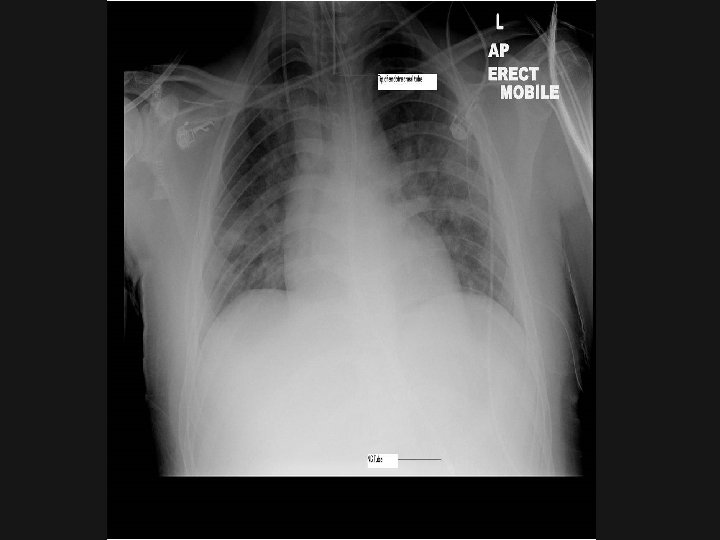

Routes Of feeding

Naso-gastric Feeding n n n Risk of aspiration in ICU: HOB 30 degrees Don’t start feed at night Risk of displacement High aspirates and inadequate calories common in ICU PEG/gastrostomy feeding for long-term

Jejunal Feeding n n n Jejunal feed: via a tube placed Trans-nasally by endoscopy, radiologically, at the bedside. Into the jejunum either at laparotomy or laparoscopy May reduce incidence of aspiration Often increases dose of EN given over NG

Access for PN n n n Usually central line in ICU – keep a clean port if PN may be needed. 5 lumen Short term PN – can have PIC (need a different formula) or PICC Long-term TPN – tunnelled subclavian catheter (Hickman) or subcutaneous port is usually inserted – OBSERVE STRICT ASEPSIS if handling these lines.

Tubes and Lines